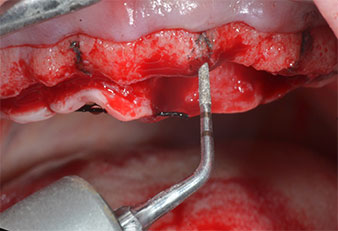

Para marcar las posiciones del implante y realizar la preparación piloto, se utilizó un inserto piezoeléctrico (Piezomed I1) con revestimiento de diamante y forma de llama (figura 3). Se tomaron precauciones para realizar movimientos hacia arriba y hacia abajo, con una potencia reducida, una irrigación completa y una baja presión (por debajo de 300 g). A continuación, se aplicó un inserto piloto (Piezomed I2A/I2P) para aumentar el diámetro inicial de 2 mm de los sitios de implante (figura 4), seguido de un inserto de 3 mm (Fig. 5).